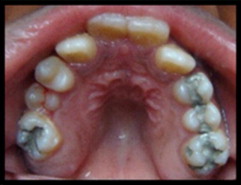

He encontrado un artículo de estudio de caso bastante interesante de A. Al-Jobair del Departamento de Odontología Pediátrica y Ortodoncia de la Facultad de Odontología de la Universidad Rey Saud, publicado en 2010. De este artículo destacaré sus partes más importantes. Este es un estudio de caso de una niña de 11 años de edad.

"La paciente parecía ser bien integrada, se la veía sana e inteligente, pero tenía dificultad para hablar. En su visita inicial tenía un tamaño de 100 cm de estatura. El examen extraoral reveló manifestaciones clásicas asociadas con la acondroplasia como ser: baja estatura, manos cortas y en tridente, prominencia frontal, puente nasal hundido, hipoplasia severa de la cara media y labios incompetentes. Se observó respiración bucal, brecha interlabial de aproximadamente 12 mm en reposo y una mente hiperactiva. El cierre de los labios no fue posible sin tensión muscular. También fue observado un perfil facial cóncavo, sin embargo, la mandíbula parecía normal y la barbilla no era prominente."

Intraoralmente, se observó macroglosia  un patrón de deglución con empuje de la lengua, gingivitis generalizada, mordida cruzada posterior, mordida abierta anterior (igual que la maloclusión) y una reacción invertida anterior. Había una relación molar dental clase III con apiñamiento (una de las complicaciones dentales más comunes en pacientes acondroplásicos) en la región maxilar anterior. La paciente tenía dentición mixta: tamaño, número y forma de los dientes era normal con múltiples lesiones y restauraciones de caries. La erupción de los dientes era compatible con la edad cronológica. La radiografía panorámica mostró un número completo de dientes permanentes, incluyendo terceros molares con desarrollo normal, apiñamiento en las regiones caninas y en los molares superiores. El análisis cefalométrico de la radiografía lateral del cráneo reveló que el maxilar era severamente retrognático (posición anormal del maxilar, cuando empuja hacia atrás, con relación al esqueleto facial y a los tejidos blandos), con la posición normal de la mandíbula, con la altura facial superior disminuida, con la altura facial inferior aumentada y con una relación esquelética de mandíbula de clase III. Dentalmente, los incisivos maxilares estaban reclinados y los incisivos mandibulares estaban normalmente inclinados. Se evaluó el riesgo de caries. El plan de tratamiento fue formulado tanto para extraer todos los dientes primarios cariados como para restaurar todos los dientes permanentes cariados. Se realizó el tratamiento dental según lo planificado, con anestesia local y la colaboración de la paciente. Esta fue colocada en un programa de visita al odontólogo a cada tres meses.

gr4 gr6 gr7